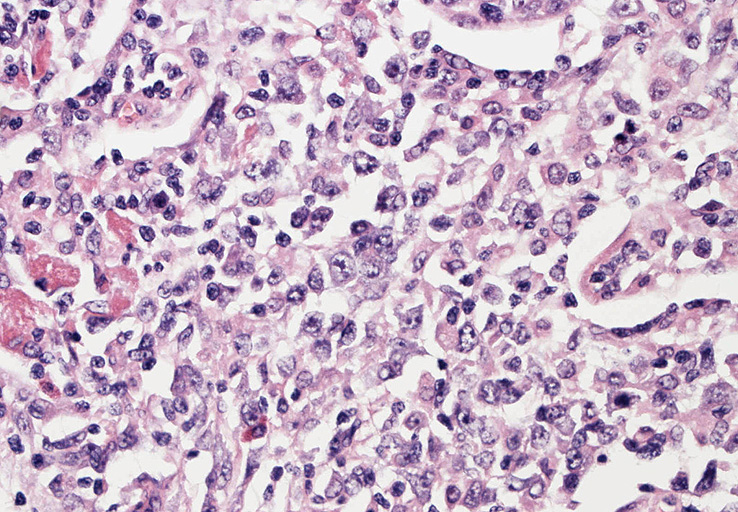

血管周囲性に大型類円形核や不整形核をもつ腫瘍細胞がシート状密に浸潤増殖している. Mitosisが多く認められる.細血管閉塞や破壊の所見がある.

間質にもシート状の腫瘍細胞浸潤がある. 大小 pleomorphicな傾向.(A, B). necrosisが認められる(C). 細気管支上皮直下まで密な浸潤あり, 小型リンパ球が混在している.(D)